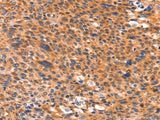

Applications WB, IHC

IHC 1:100-1:300